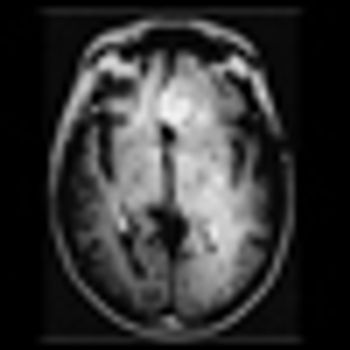

The patient is a 58-year-old woman who was diagnosed at an outside hospital with a World Health Organization (WHO) grade III non–contrast-enhancing right frontal anaplastic astrocytoma, with spread into the genu of the corpus callosum.